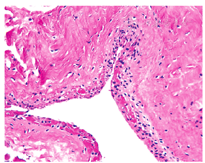

术后病理报告为致密纤维结缔组织玻璃样变,不规则增生,提示滑膜囊肿(图4)。术后患者均顺利苏醒,自觉疼痛症状轻,第2天佩带支具出院。